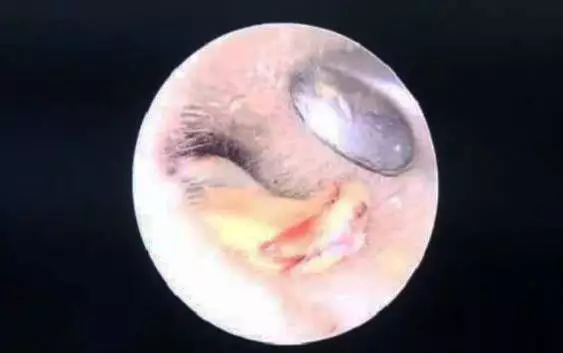

事故一: 医生诊断女孩为霉菌性外耳道炎,因为不确定菌种,还需要进行分泌物培养,再对症下药。 事故二: 杭州60岁一大爷也遇到了耳朵长毛的情况。章大爷前一天自己掏完耳朵,第二天耳朵就痛痒难忍,前来就医。 霉菌性外耳道炎和吴先生的脚气进耳朵是一个道理,都是真菌感染,只不过致病菌可能会不同。脚气的病菌多为红色毛癣菌、石膏样毛癣菌、絮状表皮癣菌、犬小孢子菌、石膏样小孢子菌、白色念珠菌......而耳朵的致病菌多为以曲霉菌、念珠菌、青霉菌及毛霉菌。 不过相同的是,这些菌都可能因为工具而带入耳朵,并在耳朵里落地生根...... 根据不同真菌种类,耳朵长出的“毛”颜色也会不一样。 曲霉菌、青霉菌感染,菌落的“毛”会是绿色的。 念珠菌、毛霉菌感染,“毛”会是白色的,程度轻的能看到一些霉丝和霉点,严重的可能会有一些脓性分泌物。 还有黑色的“毛”。不过这可能不是单一感染了某种真菌,还可能是:耳屎堵在耳朵里时间太长,让它在外耳道内潴留局部发生氧化了;陈年血痂被抠了出来;感染了黑色真菌后的团块;黑色素瘤之类的疾病(不过一般抠出来的会是黑色新生物,大多数伴有疼痛和出血)。 其实真菌进耳朵,在多数情况下都可以避免。 比如减少掏耳朵的次数。“耳屎”耵聍是保护着我们的耳朵的,它呈弱酸性的,有抑制真菌生长的作用,如果频繁掏耳朵,将耳道清理得过分干净,就会使耳道失去一层保护屏障。 用一次性采耳工具,减少交叉感染的可能。耳道也有着自己的微生物环境,当表皮葡萄球菌和棒状杆菌占多数时,耳道会更健康。如果霉菌进入耳道,菌落的平衡破坏,耳道就会真菌感染。 表皮葡萄球菌正常存在于人的皮肤、鼻腔及肠道中 棒状杆菌 如果实在觉得耳朵被“堵”住了,难受得不得不掏,又不敢自己掏,可以挂耳鼻喉科,让医生来一波专业操作! 02 硬核异物篇 玩具零件、泥土、木块金属块......总有些硬核异物在不断突破耳朵的感受。 事故三: 24岁的于先生掏因为耳朵掏不动而到医院检查,医生发现他的耳道里竟然有个算盘珠! 回溯起来,原来这颗算盘珠是他自己10岁的时候塞进耳朵的,因为当时怕被家长骂就没说而不了了之,于是这颗珠子就在于先生的耳朵里安安静静地躺了14年。 事故四: 重庆市民彭女士在给六岁的儿子豪豪掏耳朵时,发现他的耳朵里好像有异物,于是便把他送到医院检查。 医生在豪豪耳朵里取出了一棵植物种子,并且已经发芽! 医生表示,耳道里的温度是37度左右,再加上比较湿润,是适合种子生长、发芽的,这种情况如果再晚些就医,很可能会对孩子的听力造成损伤。 事故五: 以及这位心大患者,用金属硬物抠耳朵,但是金属却塞到耳道深处拿不出来了。 左方耳道亮光为金属异物,图片来自医脉通 耳道是用来传递声波的,有着一定的长度和宽度,大概长度2.5-3.5cm,粗0.7cm 左右,别看小小的几厘米,却有可能因为它弯曲的形状而藏住小东西! 成人的耳道走形略成“S”,先向前上弯曲,然后向后下,再向前下 不过为了避免进异物,耳朵也有着对策。耳道内的皮肤上分布着毛囊和耵聍腺,耵聍腺会分泌一定量的耳屎来粘附灰尘和进入的外物,耳朵里的小绒毛也会阻挡异物进入。 其实耳朵在一般情况下并不容易进入异物,如果进了东西,多数当时就会感到疼痛。 但因为每个人的外耳道长度不一样,进了东西后感受也可能不同,有的人会有异物感、阻塞感、听力改变等症状,也有的人当时感觉不到异常。 所以,蝌蚪君叮嘱一句,如遇耳朵进了异物又拿不出来,一定要及时去医院,免得自己的胡乱操作损伤了听力! 03 恐怖爬虫篇 事故六: 大连市中心医院接诊了一位60多岁的男性老人,他在前一晚睡觉时感觉耳朵里面不舒服,但没在意,第二天醒来耳朵里就像敲鼓一样。 医生检查后发现老人的耳道被一层白雾一样的絮状物封闭了,像网一样的这层絮状物背后,一个类似虫子的活物在不断地动。 原来是进入耳道的蜘蛛已经在里面结了网! 医生用专用的耳道清洗器向老人的耳道内注水清洗,一只绿豆大小的蜘蛛才被冲洗了出来。 想要避免自己碰到样的恐怖情况,最有效的办法就是保持家中卫生干净,多做蚊虫的消杀。尤其在家里经常见到小飞虫、瓢虫、蚰蜒(俗称草鞋底)、小蟑螂,需要格外保持警惕,这些虫子尤其喜欢温暖潮湿的人类耳朵! 但是如果真的遭遇虫子进耳道,千万别用土办法解决,比如滴香油、食用油、醋,还有用手电筒照亮,吸引虫子…… 这样不仅不科学,还容易造成耳道感染,让耳道内的情况更加复杂,给治疗带来难度。 04 悲伤事故篇 虽然“做完手术落下了纱布”这种传说级的事故,在普通外科手术上鲜有发生(每一场外科手术都会清点医疗用品数量),但在耳朵手术里发生的概率的确会比普通手术更高。 耳科病人做完手术后,进行术后调理和康复时一般会给病人耳部覆盖上无菌纱布,用来包扎敷料、消毒或保护手术部位,这也给将纱布、棉花误留创造了机会。 不过随着医疗水平的提高,这种小概率事件以及极少发生了,大家不必过度担忧。 05 避免耳朵生长奇怪的东西 要养成正确的卫生习惯 很多人比较享受掏耳朵的过程,前往采耳店、足疗店、按摩店掏耳朵,觉得掏完身心轻松,非常解压。 但是顾客们都同用一套工具,万一遇到消毒不到位的情况,采耳就变成了“真菌杂烩”,如同足疗传染脚气,采耳也容易将上一个客人的“耳气”带回家。 当然,也别矫枉过正,用耳毛来挡住异物(一般人做不到)。 世界上最长的耳毛50公分,其实他是患了“传男不传女”的人类外耳道多毛症 如果真的感觉自己的耳屎太多,有种堵了东西的感觉,甚至了影响听力,在医学上这种情况叫做耵聍栓塞。可以前往正规医院耳鼻喉科挂号,医生将会用药水、无影灯、内窥镜等工具进行安全可靠的“掏耳屎”(据说掏过的人在看到“成果”时都非常的爽),蝌蚪君也想尝试一二! 你耳朵曾经进过东西吗?你有听闻过身边朋友耳朵进过奇葩东西吗?他们都是怎样处理的呢?快在评论处告诉蝌蚪君吧! 审核专家:袁先道,首都医科大学北京安贞医院耳鼻喉科副主任医师,医学博士。 来源:蝌蚪五线谱